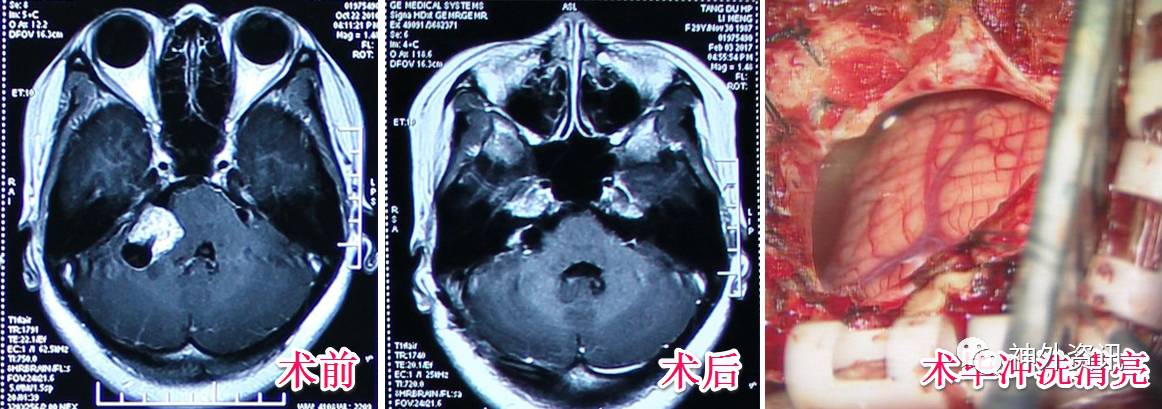

我们常规不放置引流管,除非创面或皮瓣很大的情况下放置,并要在48小时内尽可能早地拔除。当然不放置引流液也是有前提:①术后止血彻底,无任何细小渗血,反复冲洗至清亮。②严密逐层缝合,避免脑脊液渗出,影响组织愈合。而这也是对神经外科手术提出了更高的要求。